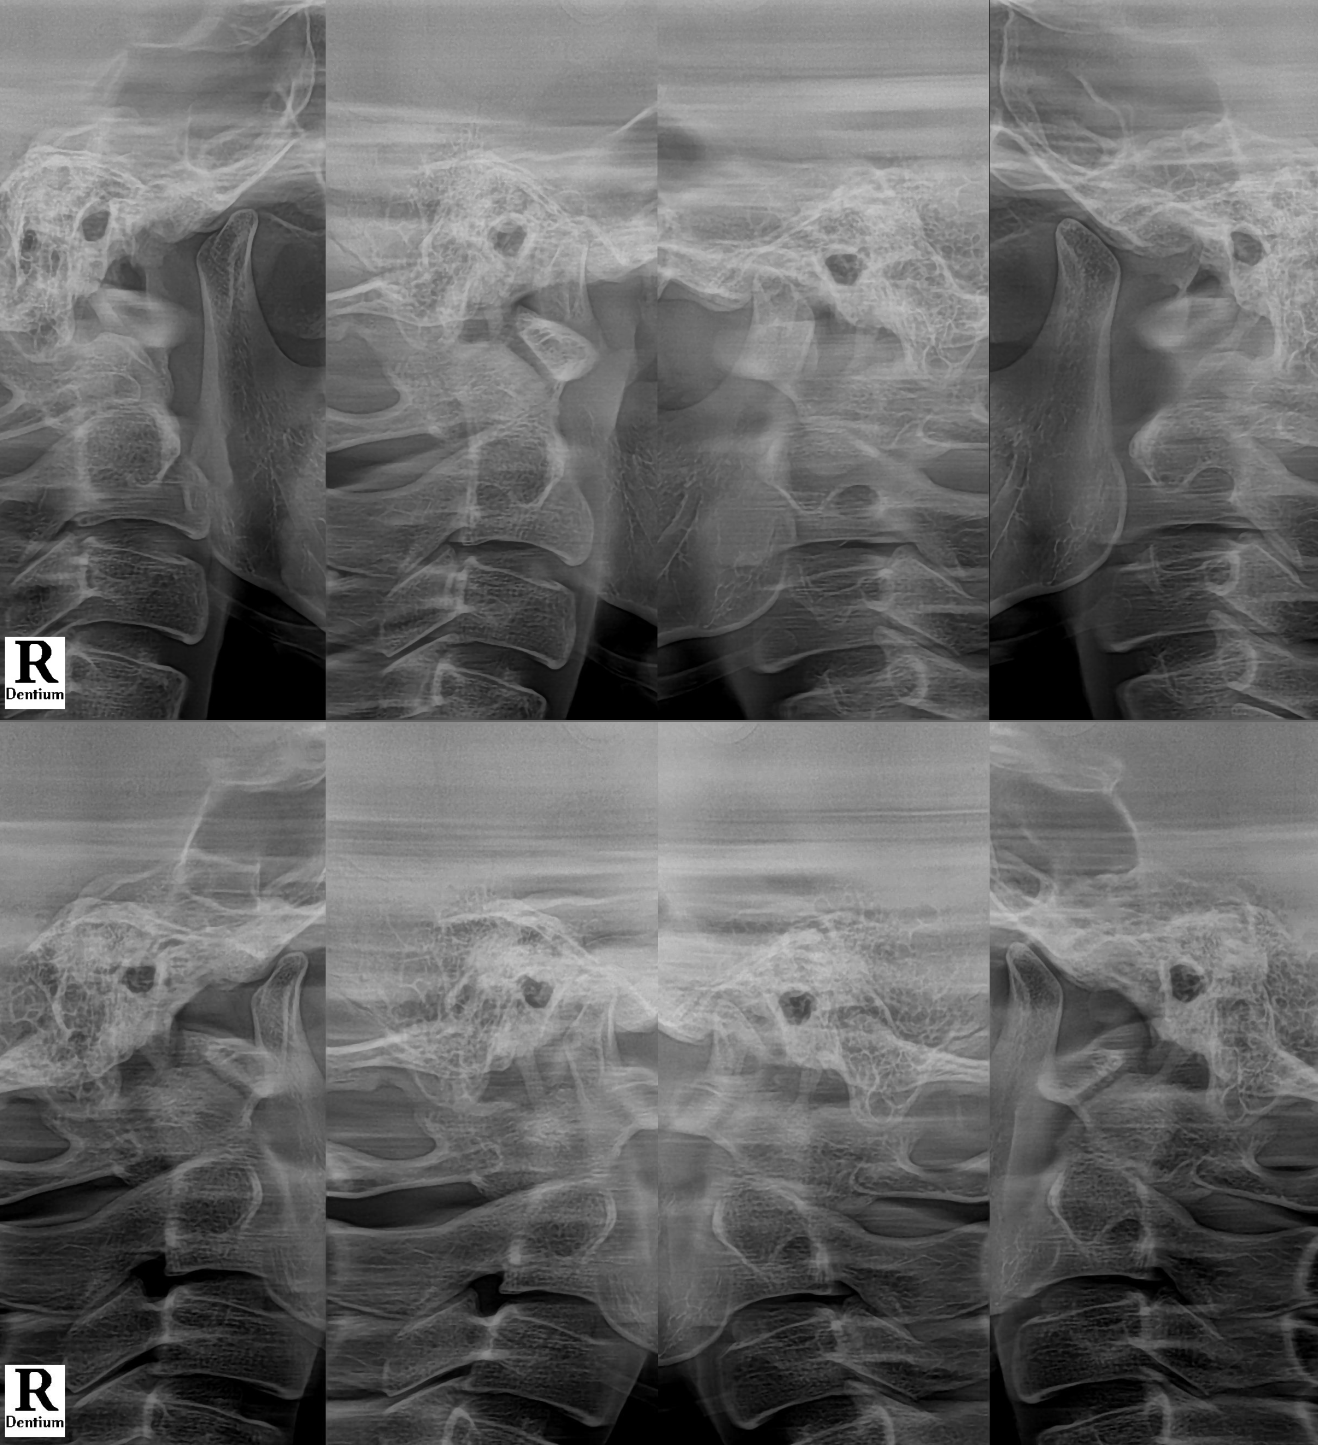

Case #210306

and the temporomandibular joint (TMJ).

👉 It is a sign of TMJ instability